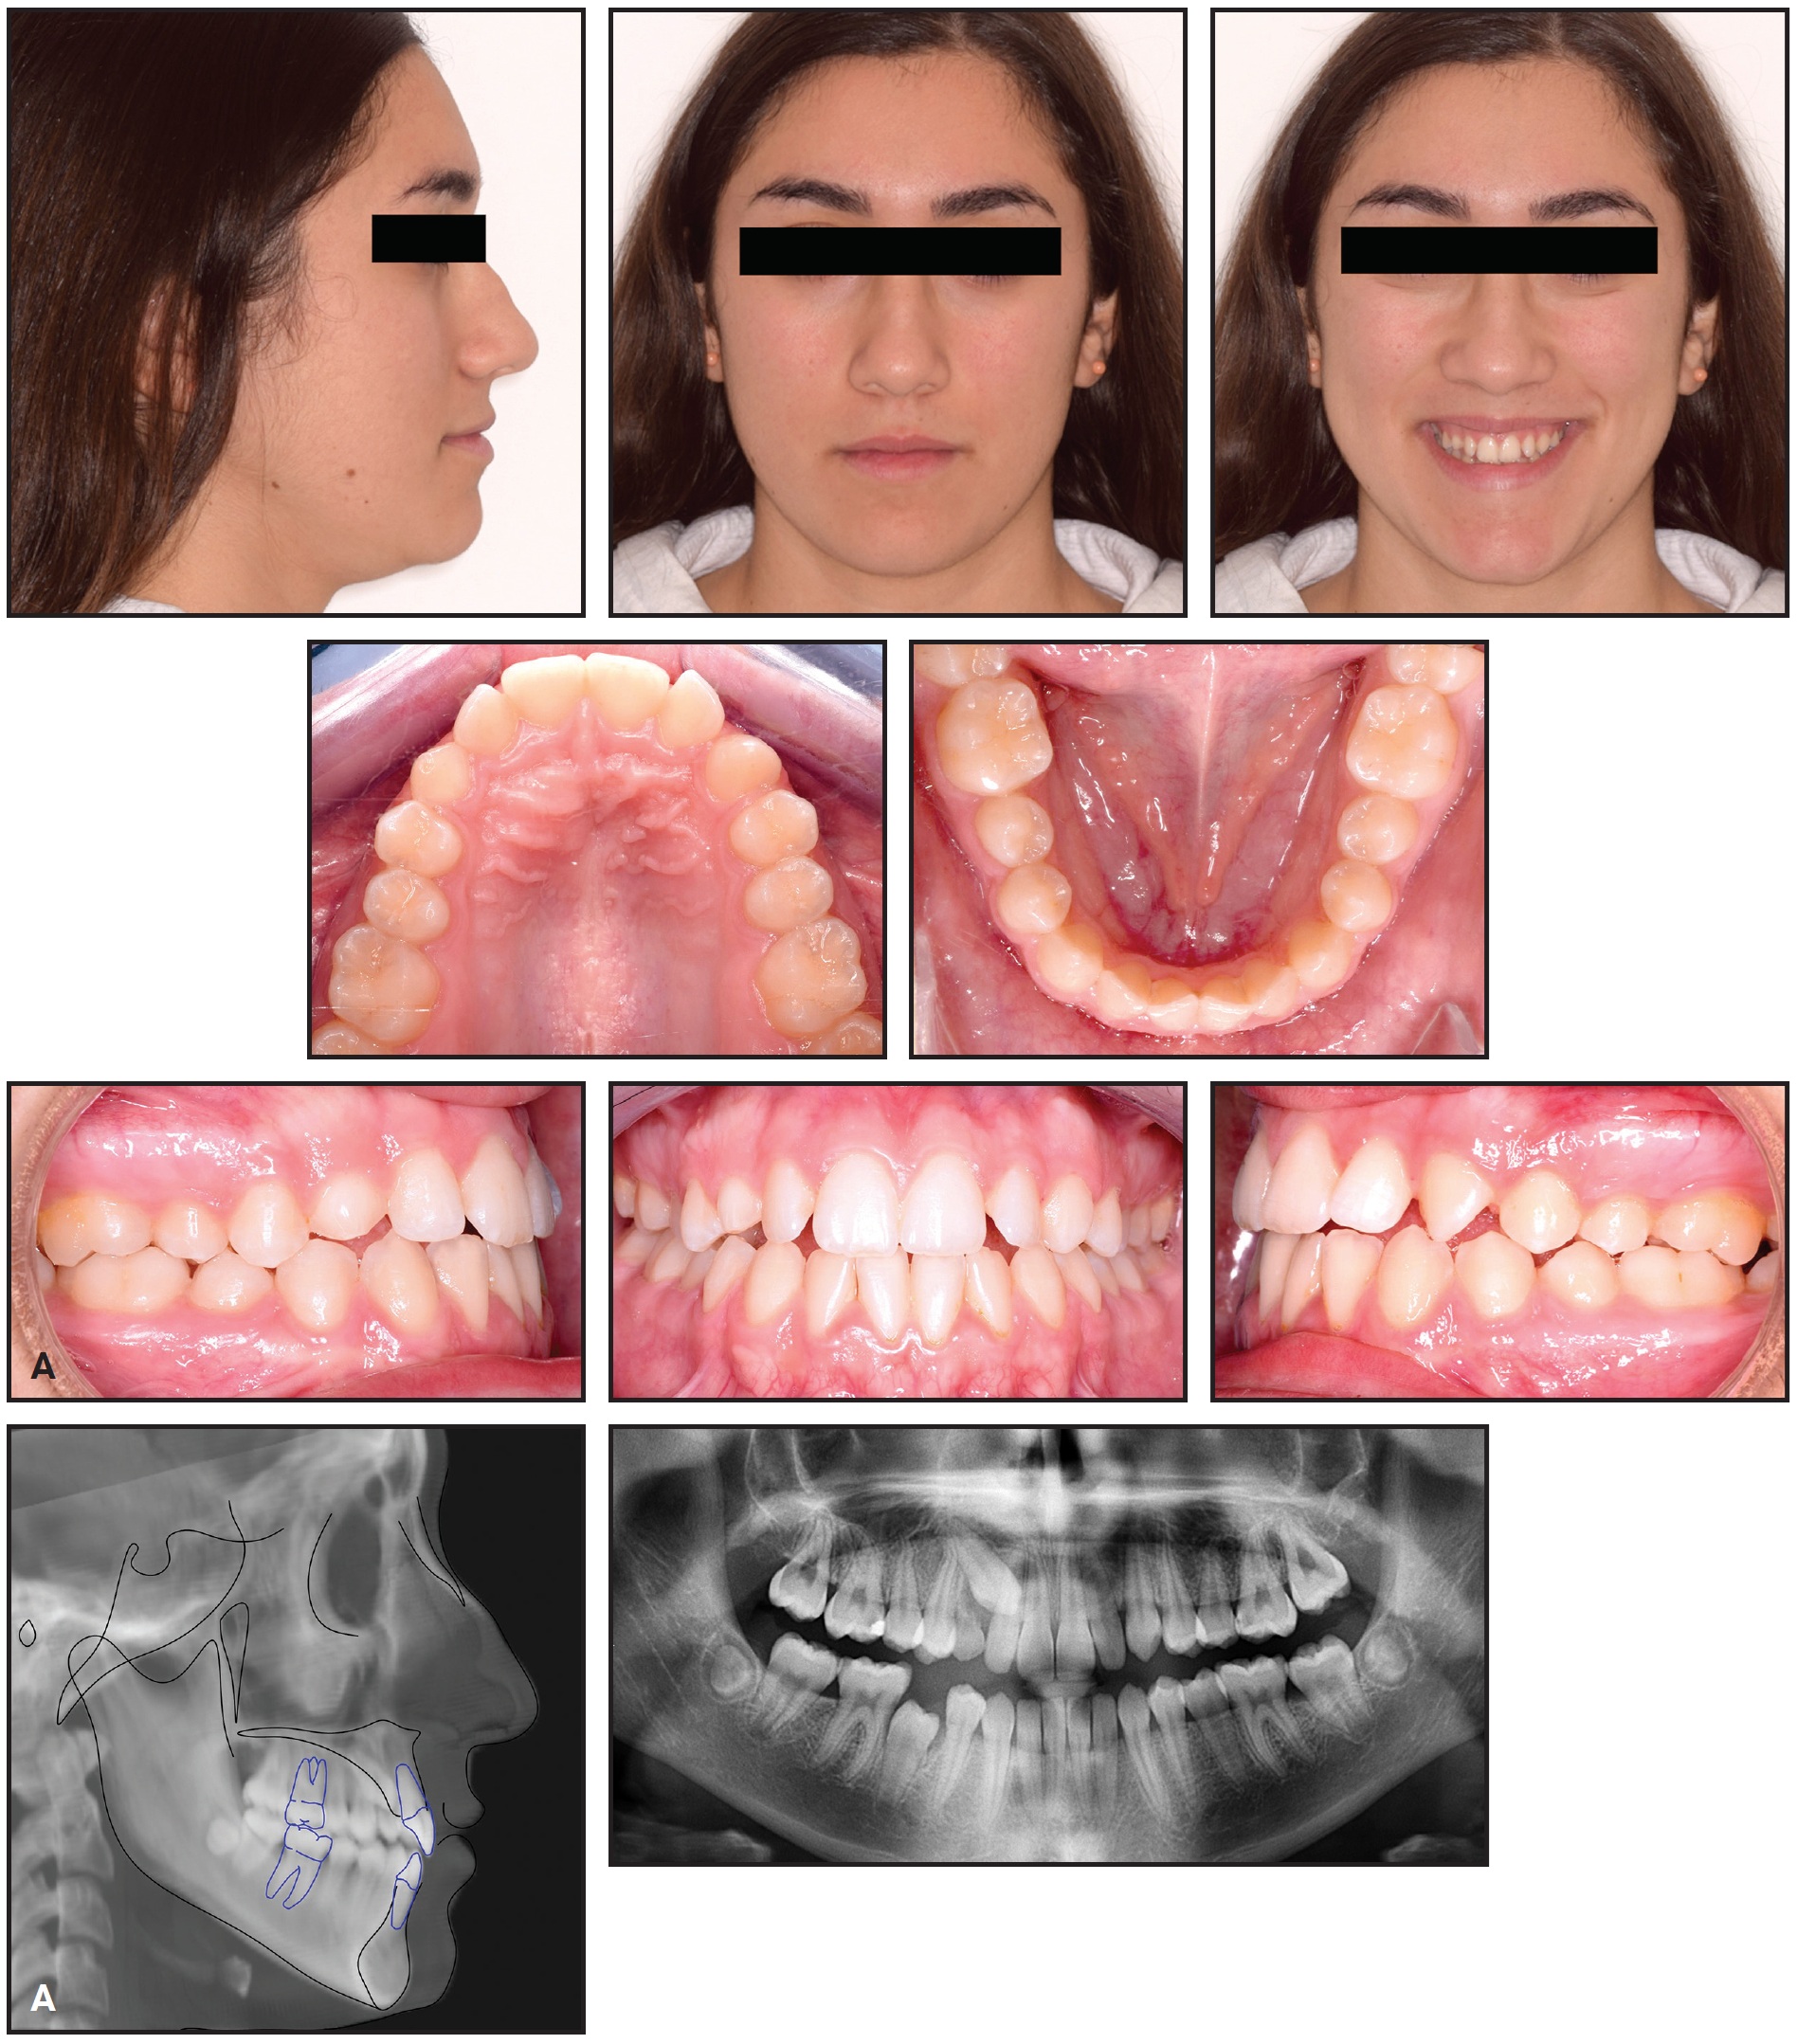

A 15-year-old female sought orthodontic treatment to improve her smile esthetics (Fig. 7A).

Fig. 7 A. 15-year-old female patient with Class I molar relationship, moderate crowding, and impacted upper right canine before treatment (continued in next image).

She displayed good facial symmetry and lateral buccal corridors on smiling, with a harmonic profile and adequate lip projection. The patient had a Class I molar relationship on both sides and moderate crowding in both arches. Cephalometric analysis confirmed good skeletal proportions in both the sagittal and vertical planes. The panoramic x-ray revealed an impacted upper right canine with mesial crown inclination. A CBCT surface rendering of the segmented maxillary teeth28 showed the canine to be in a palatal position, mesially inclined, with the crown just behind the roots of the lateral and central incisors and the root close to the apex of the first premolar. Analysis of the digital models with Maestro 3D† found excessive buccal crown torque of the upper molars and premolars on both sides, indicating dentoalveolar compensation for maxillary constriction (Fig. 7B).

Fig. 7 (cont.) A. 15-year-old female patient with Class I molar relationship, moderate crowding, and impacted upper right canine before treatment. B. Analysis of digital models shows excessive buccal crown torque of upper premolars and molars.

Initial treatment goals included skeletal expansion of the maxillary arch and de-impaction of the upper right canine with maximum anchorage. Considering the patient’s age and dentoalveolar compensation, we decided to use a miniscrew-anchored device for optimal skeletal expansion. Two miniscrews would be inserted in the anterior paramedian region of the palate to support the expander.